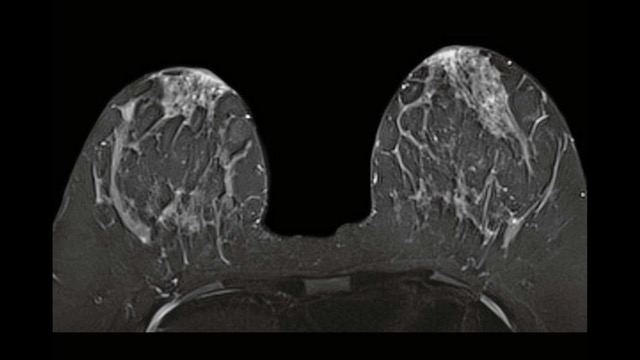

La RM Mammaria eseguita con il sistema Siemens Magnetom Vida 3T rappresenta l’eccellenza diagnostica attuale, combinando un’elevata intensità di campo (3 Tesla) con tecnologie basate sull’intelligenza artificiale per lo studio del seno.

• Alta Risoluzione Spaziale e Temporale: Grazie al campo da 3T, è possibile identificare lesioni piccolissime e studiare con estrema rapidità la vascolarizzazione dei tessuti, fondamentale per distinguere tra formazioni benigne e maligne.

Risonanza Magnetica Mammaria 3Tesla Vida Siemens IA